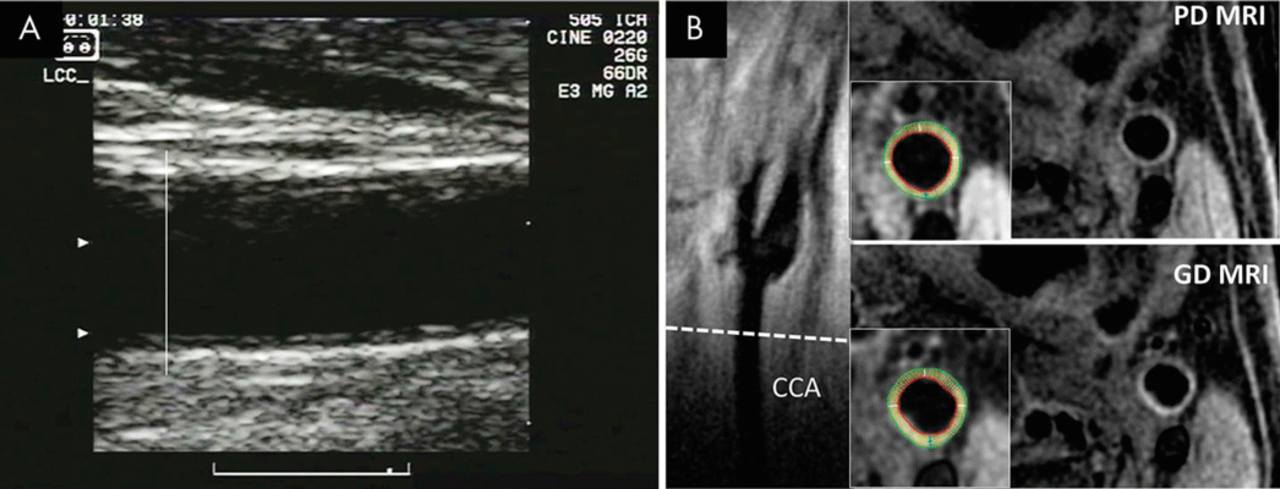

Im Gegensatz zum Ultraschall macht sie alle drei Schichten der Arterie in ihrer Gänze sichtbar. Vor allem die äußere, die Adventitia, ist interessant.

In ihr liegen kleine Gefäße, die die Arterie verdicken und die Entstehung kardiovaskulärer Erkrankungen bedingen können.

Dr. Yiyi Zhang von der Johns Hopkins University in Baltimore und Kollegen hatten in den Jahren 2000–2004 die Karotiden aller in die Studie eingeschlossenen Patienten mittels Ultraschall und MRT (mit und ohne Kontrastmittel) untersucht. Die 45- bis 84-jährigen Probanden hatten zu Beginn der Studie keine kardiovaskulären Vorerkrankungen.

Im MRT sind die drei Schichten der Halsschlagaderwand gut darstellbar. Oben die protonengewichtete Aufnahme, unten mit Kontrastmittel. Die gestrichelte Linie zeigt die Schnittebene. Im MRT sind die drei Schichten der Halsschlagaderwand gut darstellbar. Oben die protonengewichtete Aufnahme, unten mit Kontrastmittel. Die gestrichelte Linie zeigt die Schnittebene. © Radiological Society of North America